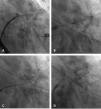

Via right femoral venous access and guided by TEE, transseptal puncture and introduction of a deflectable sheath Agilis 8.5 F Medium Curl (Abbott, IL, USA) in the left atrium were performed. A multipurpose guiding catheter 5F and straight hydrophilic guide (Terumo Europe, Leuven, BE) were introduced through it. Both defects were crossed sequentially and two 12 mm Amplatzer Vascular Plug II (Abbott, IL, USA) devices were released (Figures 2 and 3A and Video 3-6).

A: Fluoroscopy imaging showing how the guide catheter crossed the upper leak. B: Angiographic image showing the deployment of the first Amplatzer Vascular Plug II into the upper leak. C: Angiographic image showing how the guide catheter crossed the lower leak. D: Fluoroscopy image showing the release of the second Amplatzer Vascular Plug II into the lower leak.

The procedure was performed without complications, and the patient was discharged the following day with aspirin and clopidogrel. The four-week follow-up TEE showed the devices had been implanted appropriately implanted (Figure 3B).